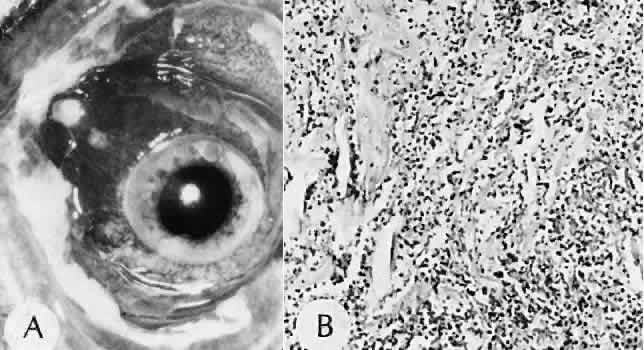

A flat anterior chamber is characterized by anterior displacement of the iris to near or in actual contact with the posterior surface of the cornea. The most common cause is leakage of aqueous along one of the suture tracks. Prolonged decompression of the anterior chamber increases the risk of synechiae formation and intractable secondary closed-angle glaucoma. Corneal endothelial damage may result in bullous keratopathy. Choroidal edema (choroidal hydrops or detachment) (Fig. 31) may be associated with a flat anterior chamber and may potentiate the condition. The choroidal edema will slow or stop aqueous production by the ciliary body, further delaying reformation of the anterior chamber. The histologic characteristics of choroidal edema consist of spreading of the choroidal tissue in a fanlike configuration and eosinophilic fluid filling the intervening spaces. The edema fluid may be lost in processing, leaving multiple apparently empty spaces.

Fig. 31. A case of choroidal detachment. A. By fundus reflex, a large dome-shaped mass can be seen originating from the choroid. The differential diagnosis would include uveal malignant melanoma. In this case, the clinical findings were due to choroidal detachment from the sclera because of fluid accumulating in the suprachoroidal space following cataract surgery. B. The histologic section from another case of choroidal detachment illustrates the location (arrow) and extent of the detachment. In this case the detachment extends to the region of the ciliary body limited anteriorly by the attachment of the choroid to the scleral spur. The displacement of the ciliary body will result in apparent shallowing of the anterior chamber. (Hematoxylin-eosin stain; × 6.)